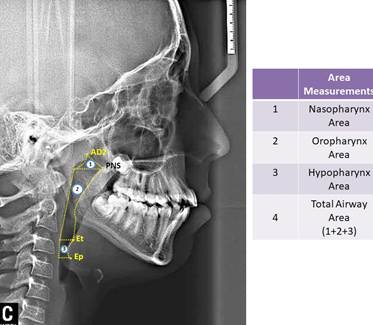

In study, 35 cephalometric points (Figure 1), 8 cephalometric planes, and 30 cephalometric measurements (Figure 2) were used. In the cephalometric analysis; 5 craniofacial, 8 nasopharyngeal, 7 oropharyngeal, 2 hypopharyngeal (Figure 3), 9 hyoid measurements (Figure 4) and 4 area measurements (Figure 5) were used.